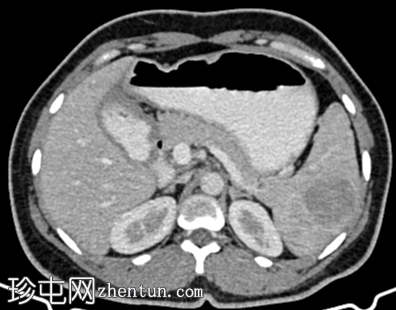

冠状位增强扫描

动脉期

脾脏内可见一圆形低密度病灶,动脉期呈周边环状强化,延迟期呈轻微向心性充盈

未见钙化、动静脉畸形或动脉瘤

学特征为:病灶周围呈放射状强化,中心呈放射状强化,周围环状强化,中心充盈轻微。增强扫描后可见中央星状瘢痕。